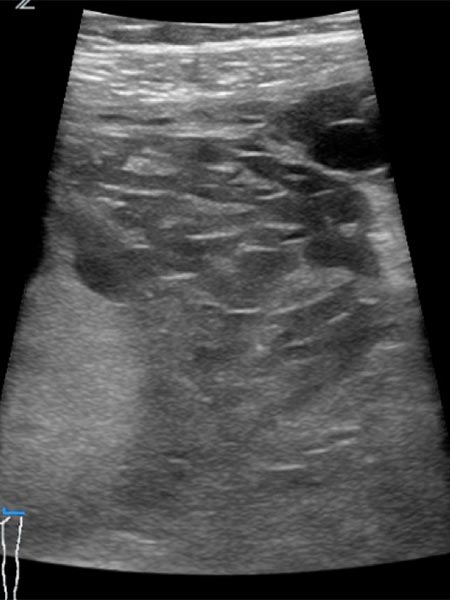

Bildgebung vor der Schwangerschaft im Ultraschall mit 10,4 MHz Linearschallkopf. Nachweis einer intramuskulären subfaszialen venösen Malformation mit multiplen echoverminderten Venenkonvoluten.

In der 21. Schwangerschaftswoche dann deutliche Vergrößerung der venösen Malformation im Ultraschall mit 10,4 MHz Linearschallkopf. Progredienz der intramuskulären subfaszialen venösen Malformation mit multiplen echoverminderten Venenkonvoluten und deutlicher Strukturauflockerung der echoverminderten und nun zum Teil auch echovermehrten Venenkonvolute durch Gerinselbildung.